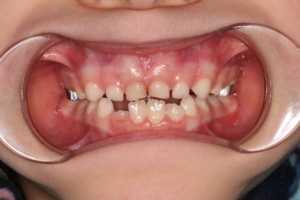

Аппарат Хааса один из немногих ортодонтических аппаратов , который позволяет достигнуть скелетного расширения в период активного роста ребёнка. Чем это обусловлено? Верхняя челюсть состоит из двух половин, которые связаны нёбным швом (хрящ). Именно он является зоной роста верхней челюсти. Воздействуя на эту зону : разрывая, растягивая её, стимулируется скелетное расширение. Но оно возможно до определённого возраста, пока шов не окостенеет. Поэтому данный ортодонтический аппарат используется в среднем от 5 до 12 лет.

В каких случаях показано применение аппарата Хааса?

1. Резкое сужение верхней челюсти

2. Большой дефицит места для постоянных зубов